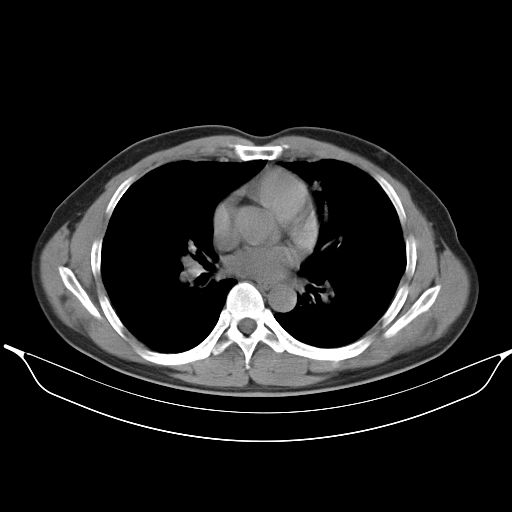

标题: CT25490:男,40岁,体检发现;无其它不适。 [打印本页]

标题: CT25490:男,40岁,体检发现;无其它不适。

考虑右下肺周围性肺癌并肺内多发转移,纵隔淋巴结转移!

支持 !考虑右下肺周围性肺癌并肺内多发转移,纵隔淋巴结转移,(气管前腔静脉后,隆突下,主动脉弓下都有了)